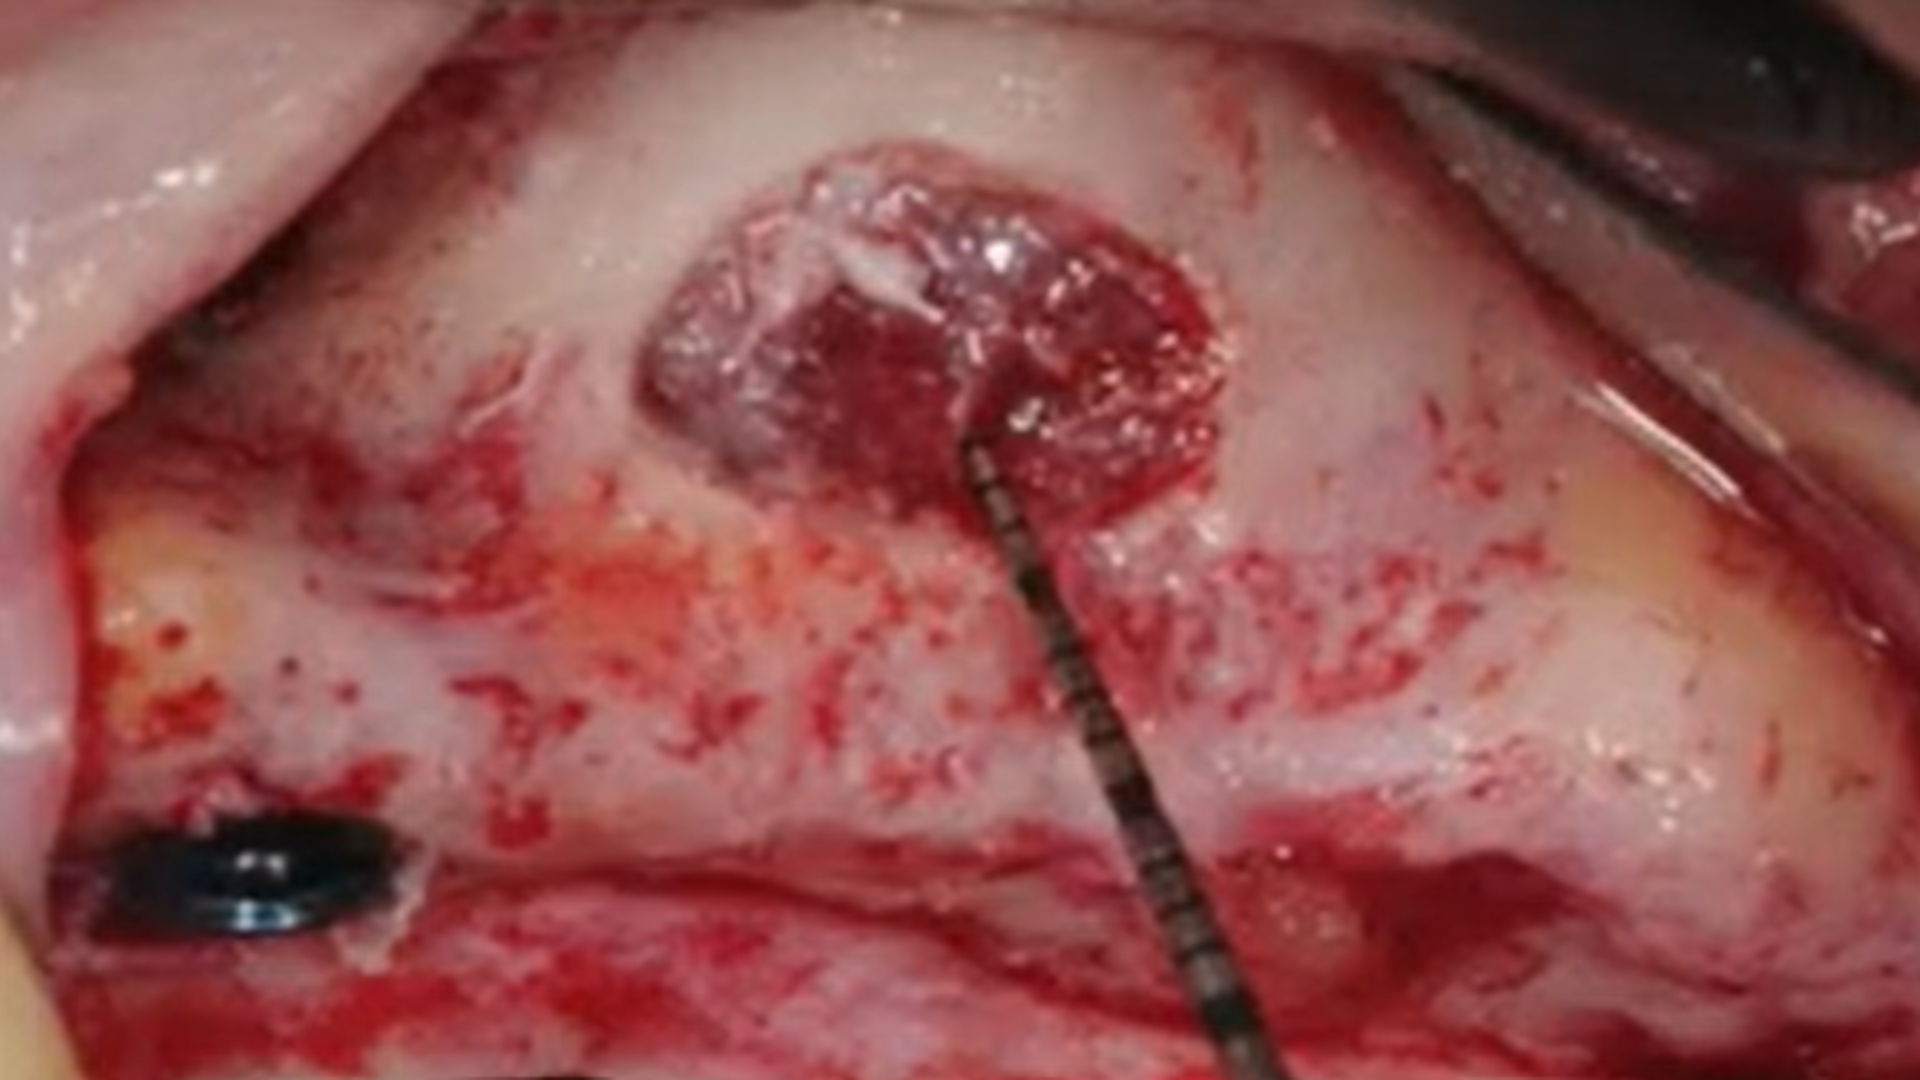

Sinus membrane perforations

Example of different clinical cases: step-by-step surgical protocol

Osseodensification technique